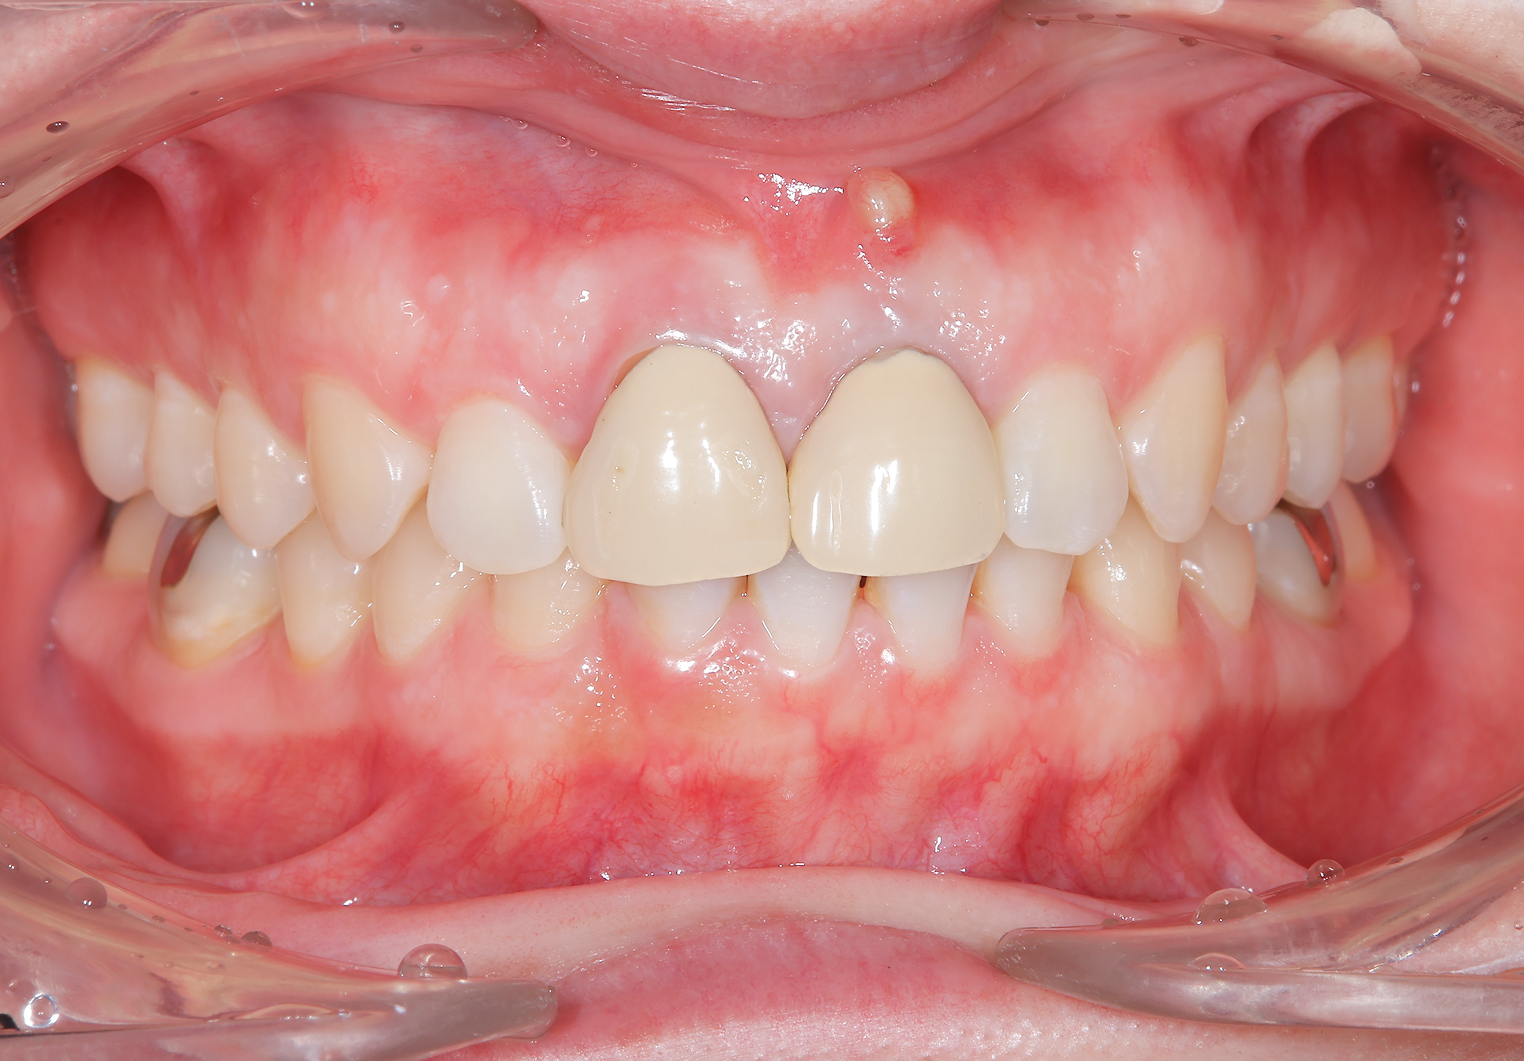

主訴:前歯の歯茎にできものができた。

治療概要:左上(写真では右)の真ん中の歯、根元の方にニキビのようなできものができています。診査の結果この歯は根が割れており、抜歯と判断しました。

治療前

治療後

前歯2本がインプラント治療に至った背景

お口全体を検査したところ、自覚はありませんでしたが、右の前歯もレントゲンを見ると歯の根の中腹あたりが溶けてしまっています。この歯も残念ながら抜歯となると判断しました。